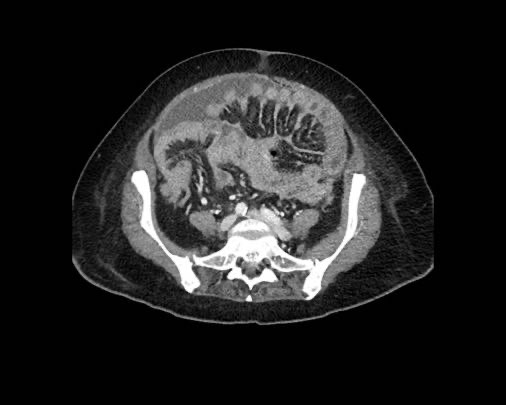

Ca lâm sàng 2

Cuộn qua các lát cắt.

Bạn có thể phát hiện tất cả các tổn thương cấy ghép phúc mạc không?